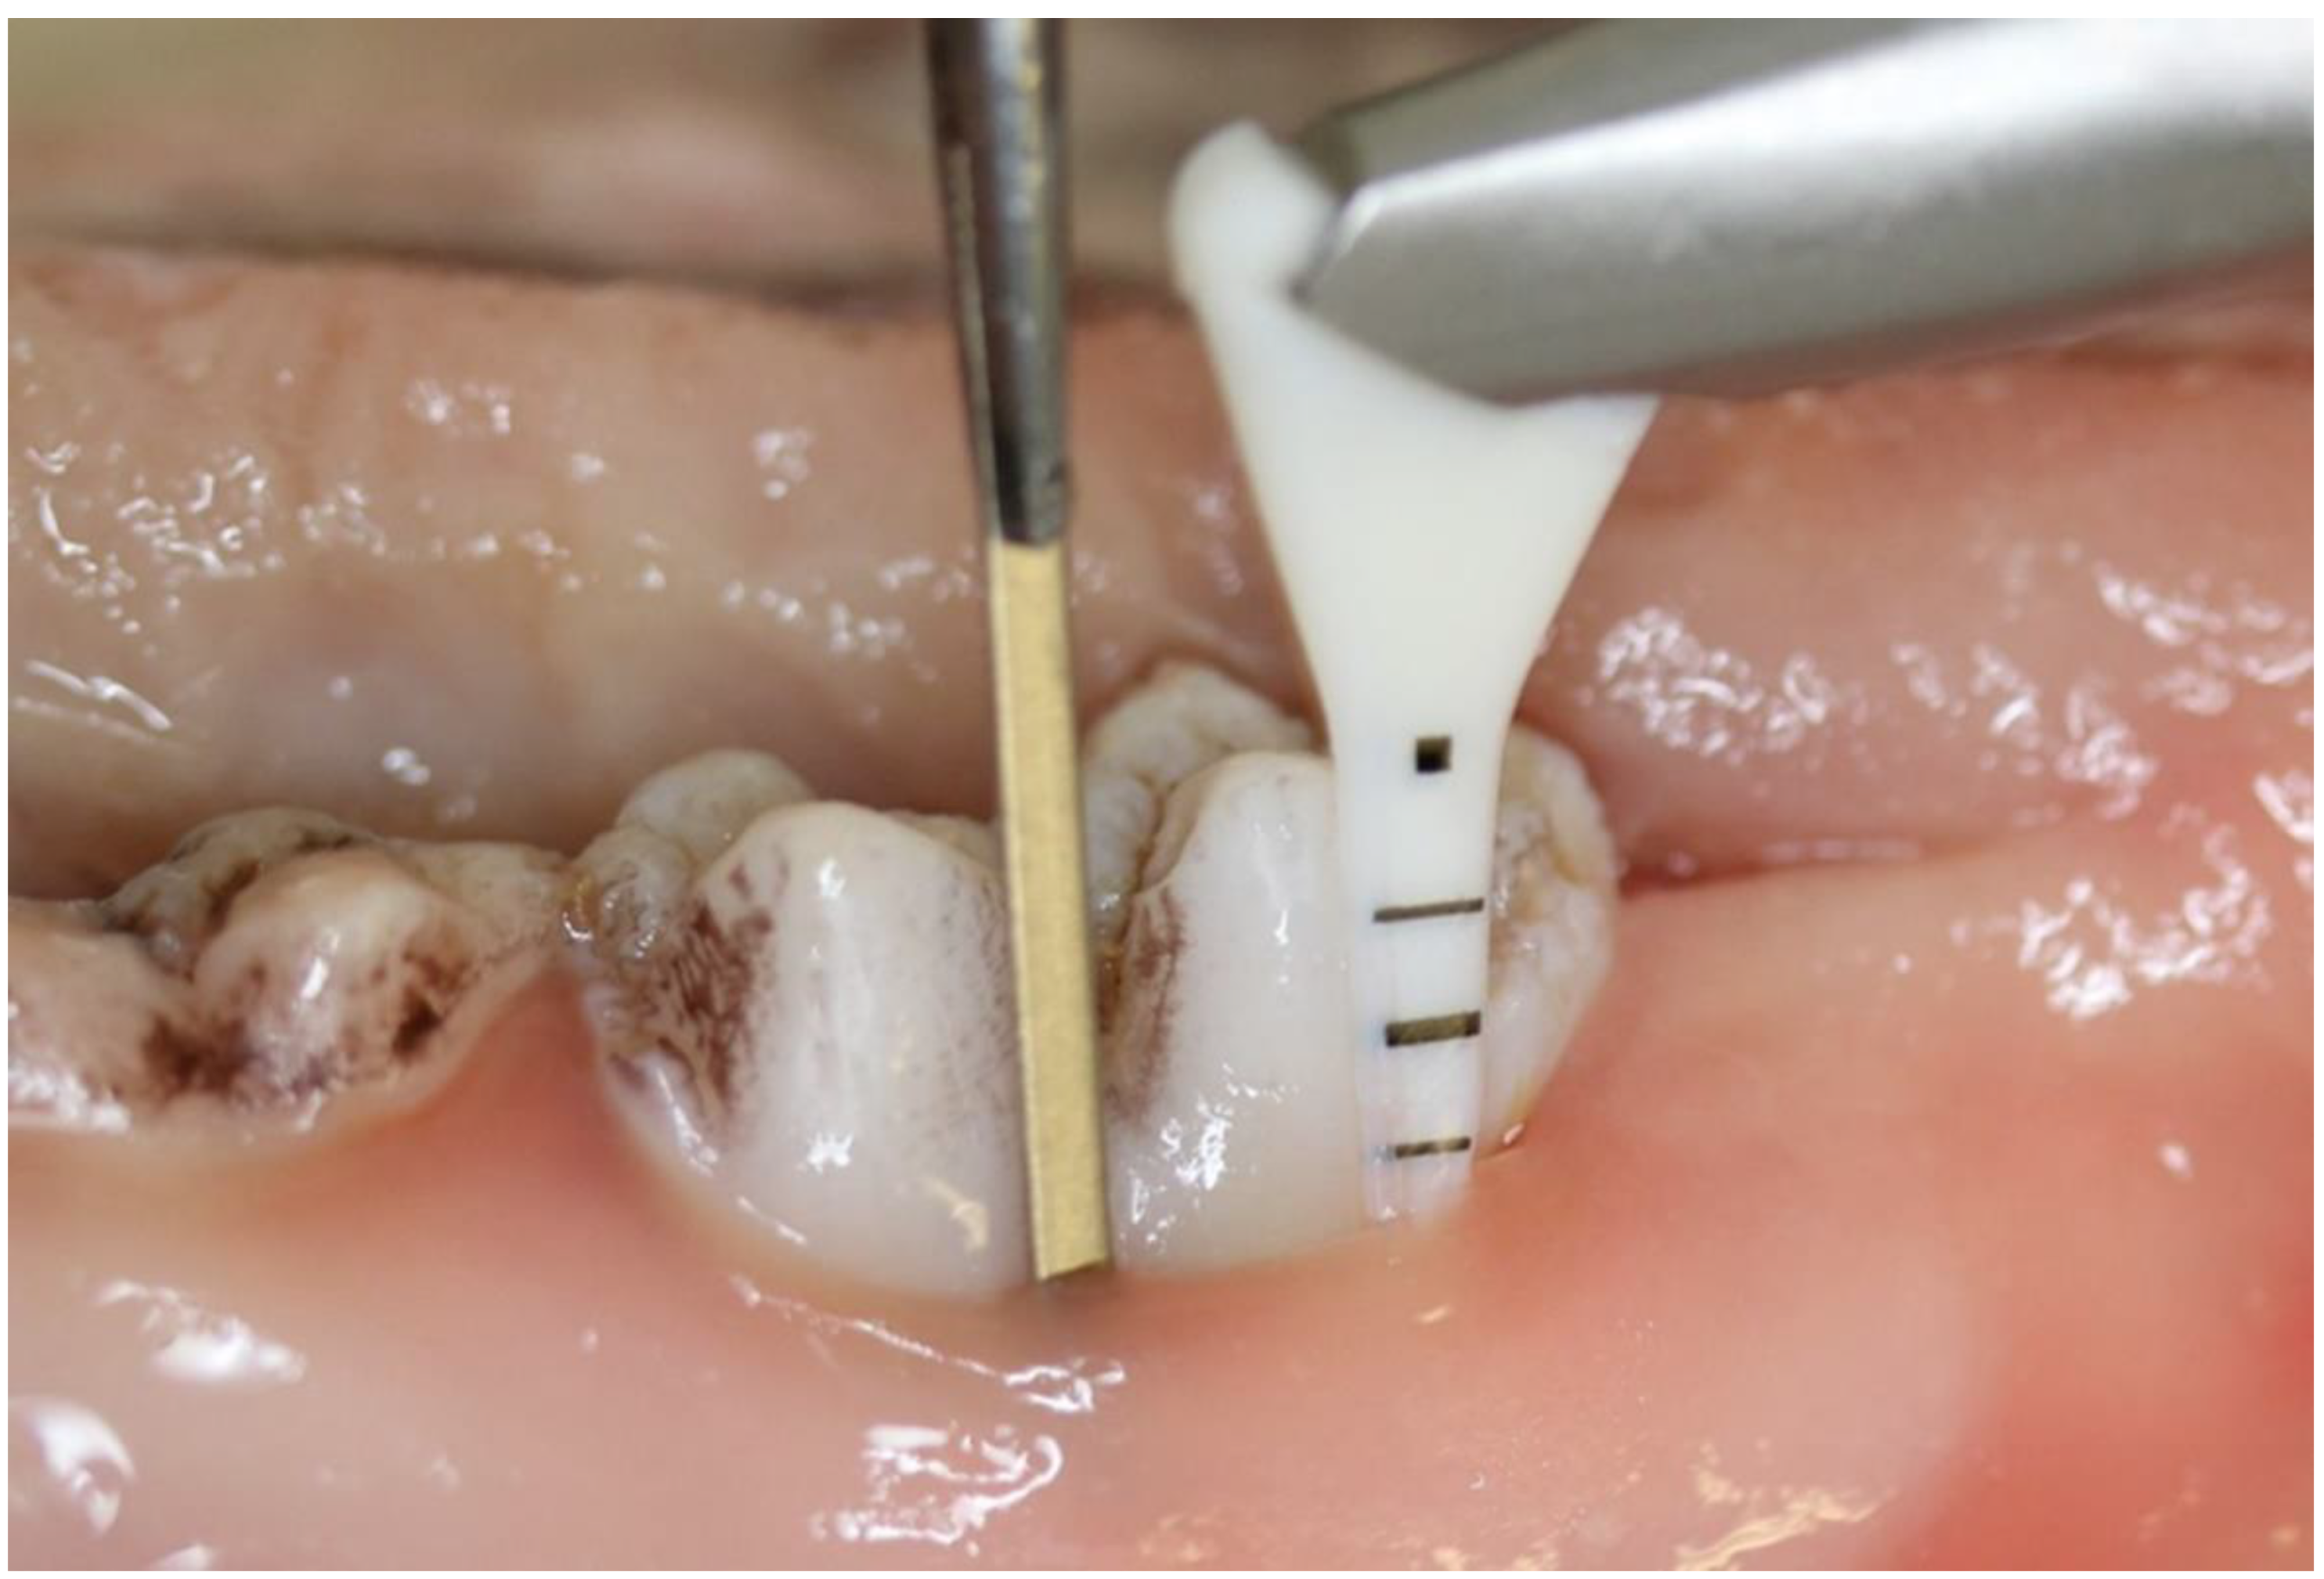

2. Materials and Methods

2.1. Experimental Design